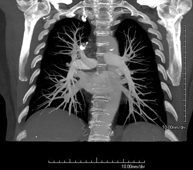

Prova diagnòstica que consisteix en l'estudi de les artèries pulmonars mitjançant l'ús d'un equip de TC (Tomografia Computeritzada) per obtenir imatges bi i tridimensionals. En aquest estudi és imprescindible l'ús de contrast iodat que permet una millor definició anatòmica. Aquesta prova està principalment indicada en els casos de sospita de tromboembòlia pulmonar (TEP) per descartar o confirmar la presència de coàguls sanguinis a l'interior de les artèries. - TC Tòrax d'alta resolució

Diagnostic test to examine the pulmonary arteries using CT (Computed Tomography) equipment to obtain two- and three-dimensional images. The use of iodinated contrast is essential in this study, as it will allow for better anatomical definition. This test is mainly indicated in cases of suspected pulmonary thromboembolism (PTE) to rule out or confirm the presence of blood clots inside the arteries.